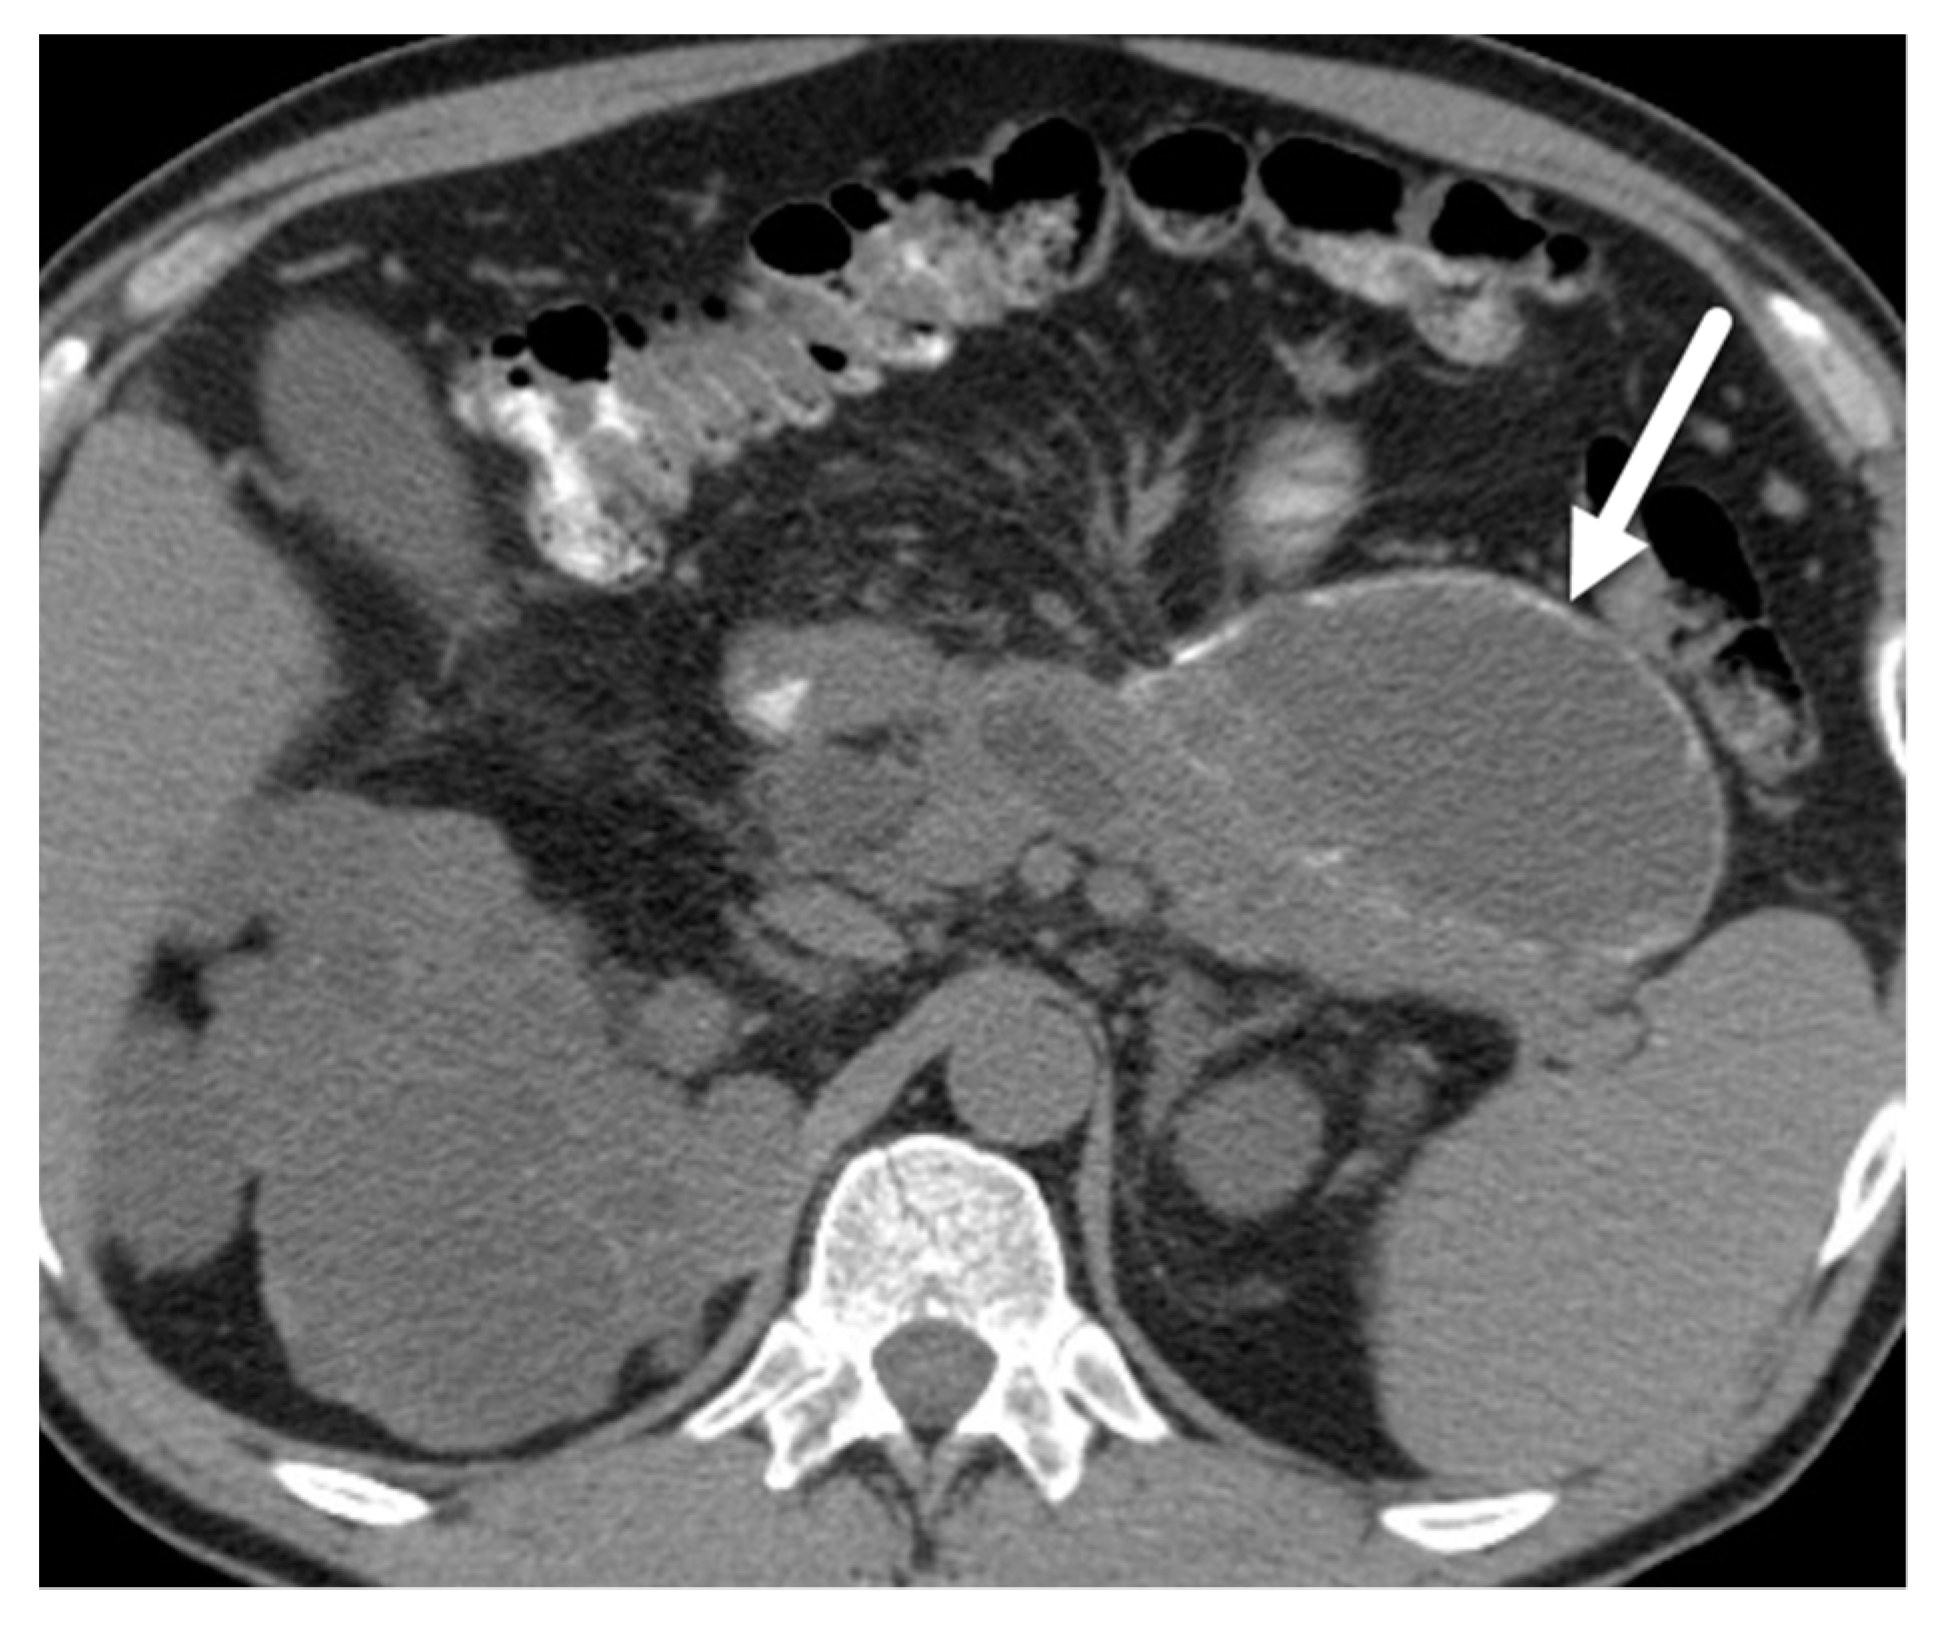

- Ren, F.; Zuo, C.; Chen, G.; Wang, J.; Lu, J.; Shao, C.; Hao, X. Pancreatic retention cyst: Multi-modality imaging findings and review of the literature. Abdom. Imaging 2013, 38, 818–826. [Google Scholar] [CrossRef]